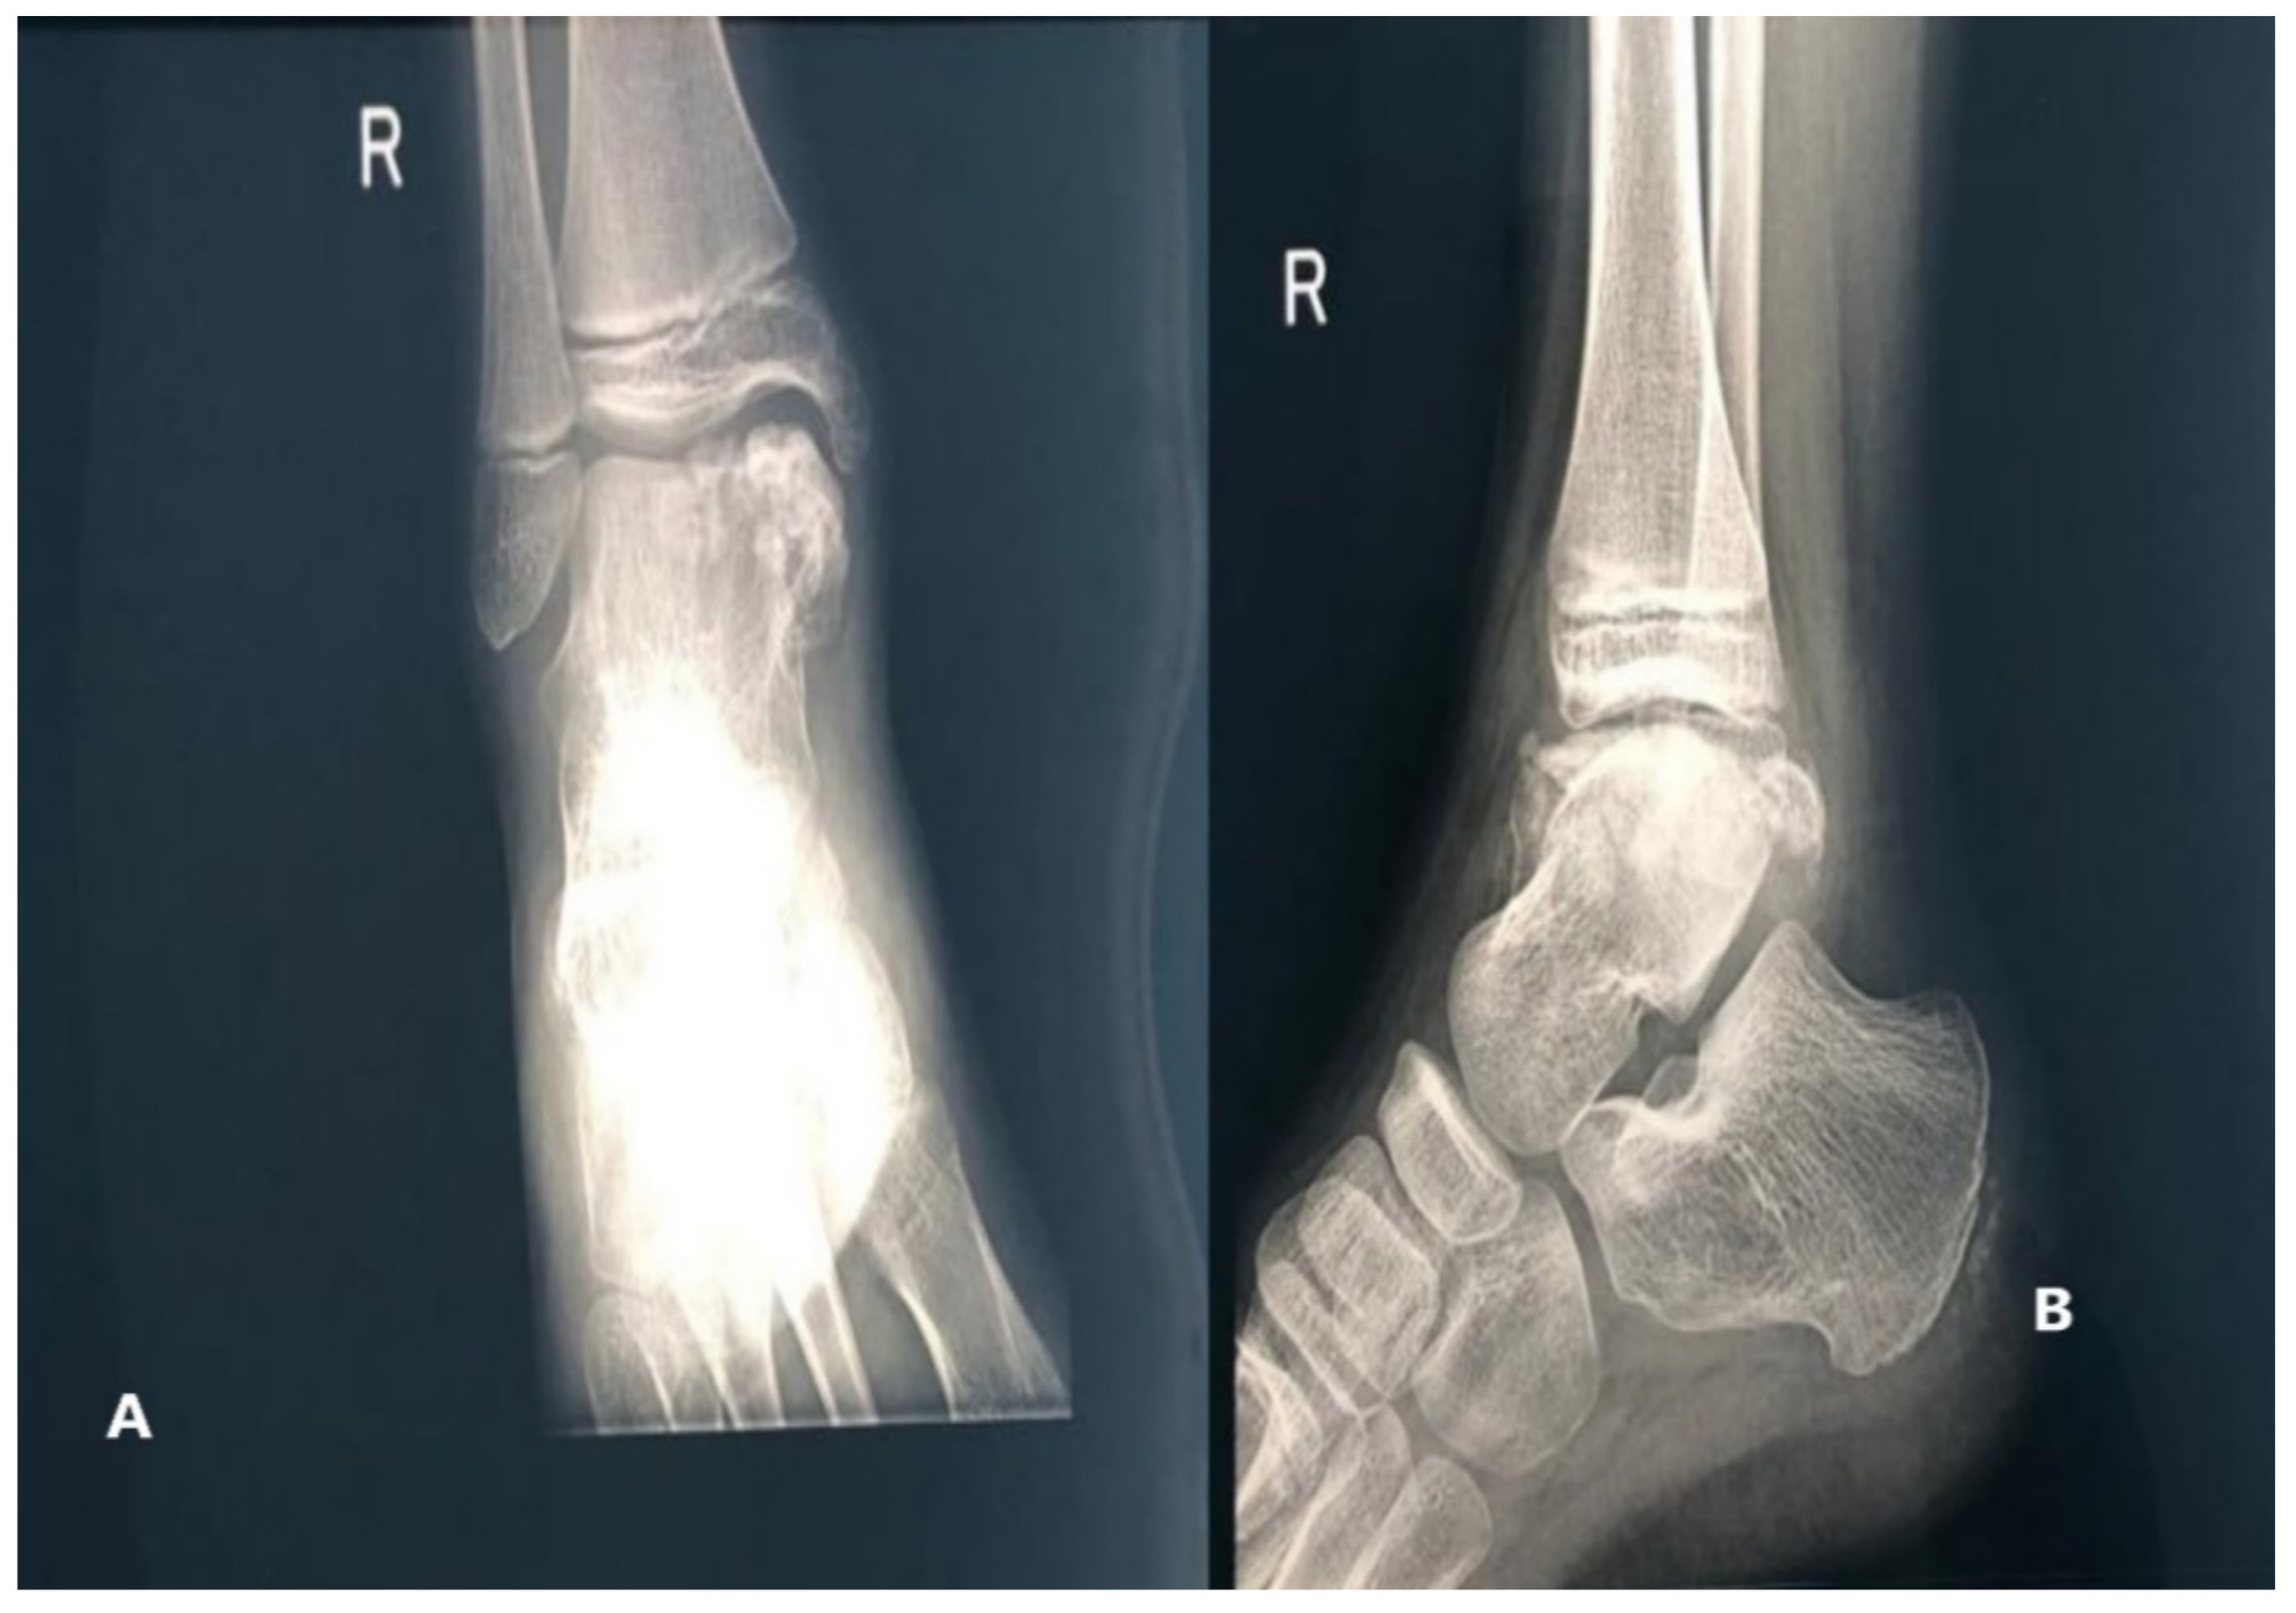

The X-ray showed multiple nonuniform ossification centers, osteochondroma-like near the right talus, anterior, posterior, and on the medial side of it, separated from the talus and the distal tibial epiphysis, deforming the articular surface on the medial side of the right tibia Figure 2.

The X-ray of the ankle revealed a bone-like mass composed of multiple ossification centers near the left talus and the peroneal malleolus, extending posteriorly, apparently originating from the talus. There was no periosteal rection or invasion of the soft tissue surrounding the tumoral mass (Figure 13).

Figure 2. Radiologic images of Patient no 1. (A) Anteroposterior view (B) Side view.

Figure 13. (A) anteroposterior view X-ray, showing a bony tumoral mass arising from the talus and extending to the peroneal malleolus; (B) multiple ossification centers and an overgrowth of the left talus.